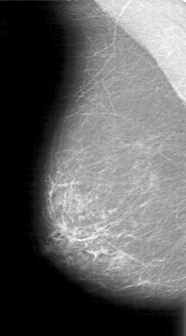

D_4047_1.RIGHT_CC

RIGHT_CC LINES 5281 PIXELS_PER_LINE 2926 BITS_PER_PIXEL 12 RESOLUTION 43.5 NON_OVERLAY